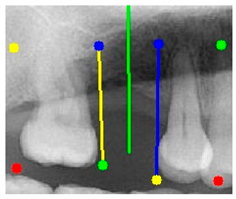

The angle bisector of the two auxiliary lines was then calculated using the angle bisector formula shown in (8), where (, , ) and (, , ) represent the coefficients of the two lines. The resulting internal angle bisector defines the preliminary implant pathway orientation derived by this framework. This bisector represents the most stable implant pathway orientation direction, ensuring that the implant avoids adjacent teeth and critical anatomical structures while maximizing bone–implant contact area. Such orientation enhances osseointegration stability and prevents complications from improper angulation, such as malocclusion or uneven stress distribution. The visualization of this process and the algorithmic design are presented in Figure 8. Finally, the auxiliary pathway generated by the algorithm was compared and overlapped with the implant pathway orientation annotated by dentists on the images to evaluate the predictive capability and accuracy of the model. The overlap results serve as a basis for further model optimization and provide valuable reference information for clinical application.

Figure 8.

Auxiliary lines are derived from adjacent teeth, the blue and yellow line is the result of implant pathway orientation visualization algorithm, and the green is the best implant pathway orientation.

3.3. Comparison with Clinical Ground Truth and AI-Assisted Framework

This subsection presents a comparison between the dentist-defined clinical gold standard and the predictions generated by our AI-assisted framework to evaluate the reliability of implant pathway orientation. The result is shown in Table 10, the preserved DPR validation set was used for verification, and the AI-assisted framework results were overlaid onto the original DPR images to provide a clear visualization. The AI-assisted framework pathways (green lines) were highly consistent with the dentists’ ground-truth annotations (black lines). Quantitatively, the mean squared error (MSE) between the predicted implant direction and the dentists’ planned results was only 1.537° across multiple test images. This minimal deviation validates the proposed system’s technical feasibility. It highlights its clinical potential to provide accurate and stable guidance for implant placement, thereby reducing the risk of misalignment and supporting efficient preoperative orientation.